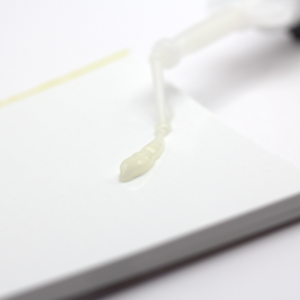

Colle composite définitive

Composite de collage définitif auto-mordançant / auto-adhésif pour céramique.

> Collage esthétique des facettes, grâce à la fine épaisseur du film (10µm)